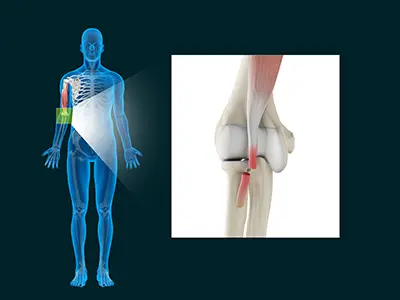

Ulnar Collateral Ligament (UCL) Injury

The ulnar collateral ligament (UCL), also called the medial collateral ligament, is located on the inside of the elbow and connects the ulna bone to the humerus bone.

UCL Reconstruction (Tommy John Surgery)

Commonly called Tommy John surgery, this procedure involves reconstructing a damaged ligament on the inside of the elbow called the ulnar or medial collateral ligament